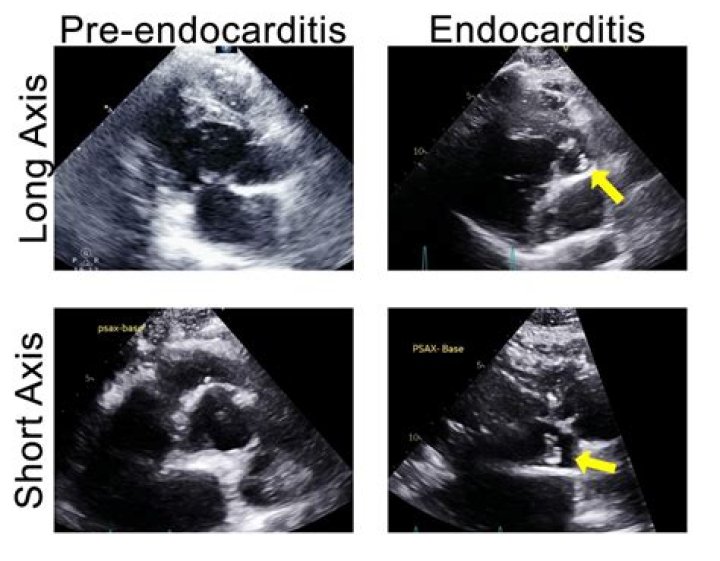

Three echocardiographic findings were considered to be major criteria for the diagnosis of endocarditis: (1) presence of vegetations defined as mobile ech...